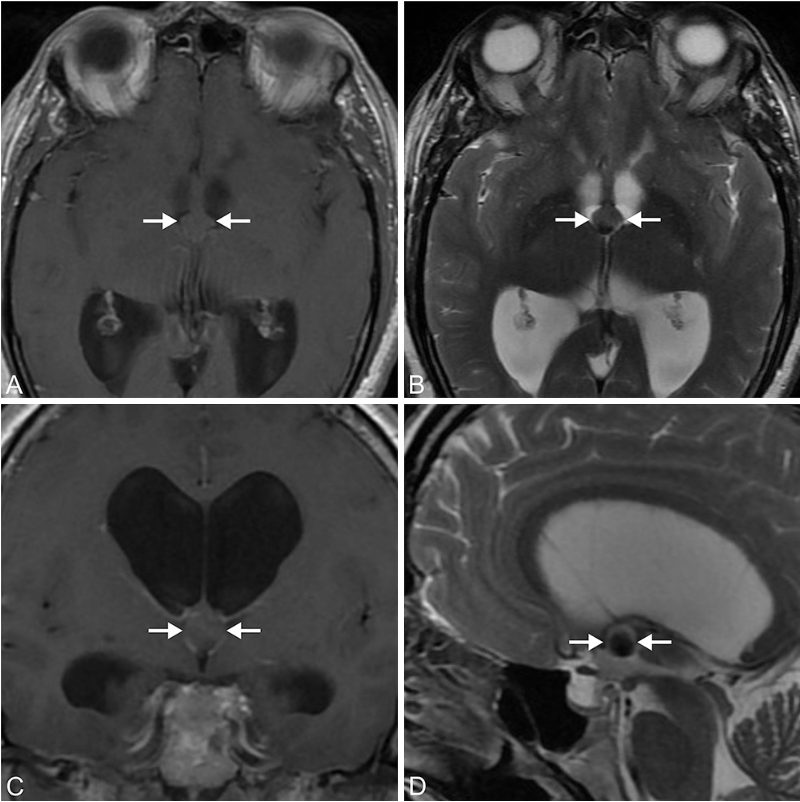

一名8岁的男孩,由于中脑导水管处的一个肿瘤压迫而出现严重的...